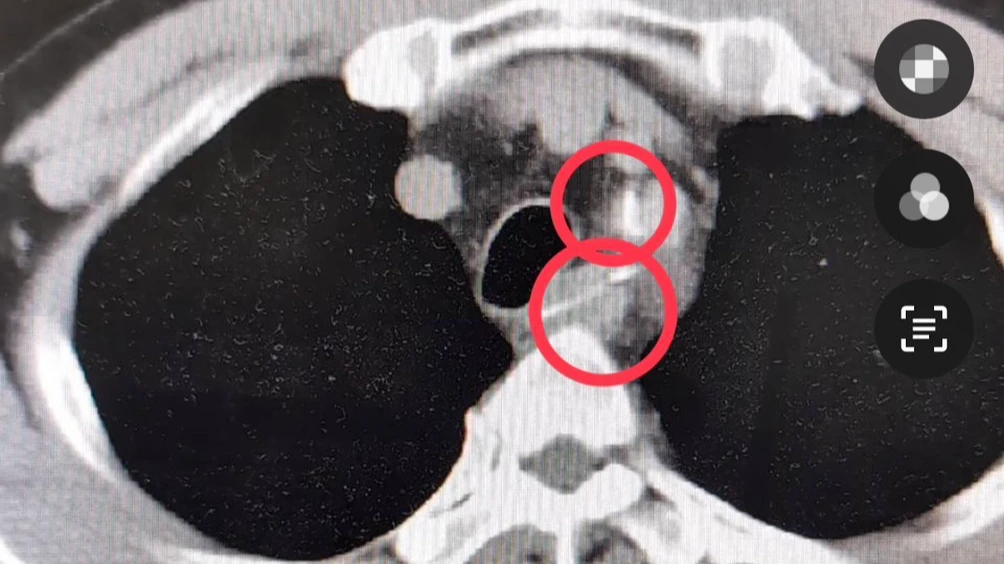

由於患者主訴胸痛且收縮壓約170mmHg、舒張壓約95mmHg血壓偏高,急診團隊第一時間懷疑是心肌梗塞或主動脈剝離,隨即安排抽血、心電圖、胸部X光及電腦斷層等檢查,結果在影像中清楚看到食道內卡著兩根尖銳異物,經會診腸胃科醫師王允成進行內視鏡檢查後,成功夾出兩根長約3公分、如50元銅板直徑的魚刺。